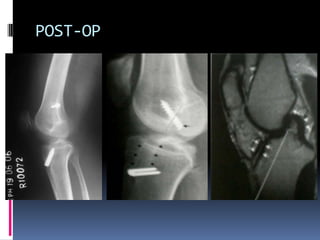

POST-OP

Bony Tunnels are very precisely drilled in the tibia and femur to recreat

the normal anatomic position of the ACL . The graft is passed and

secured in bones.